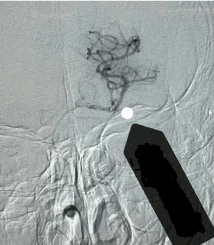

Endovascular thrombectomy: microcatheter through the occluded artery, micro catheter trace imaging showed again in the arterial lumen, distal blood flow is good, as shown in Figure 4. Then, according to the diameter of the lesion, the SolitaireAB 4 mm×20 mm or SolitaireAB 6 mm×20 mm (EV3, Inc, USA) was placed in the lesion, as shown in Figure 5. The stent and microcatheter were then removed simultaneously to the guide tube, and the catheter was removed from the body, and the thrombus extracted by the Solitaire stent was examined, as shown in Figure 6. If necessary, take the bolt several times, and then check the angiogram to see if the blood vessel is Complete recanalization after the thrombus is completed (Figure 7).

Figure 4. Microcatheter imaging showed good blood flow in the distal end of the artery

If the angiography showed that the vessel wall was basically smooth, and the main branches were smooth, the flow rate and flow rate were basically normal, as shown in Figure 7, thrombectomy was completed.